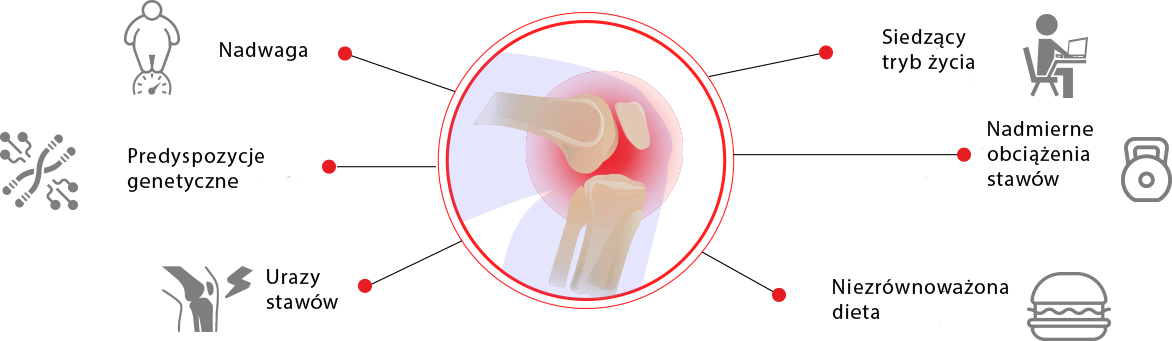

Istnieją tylko 2 główne przyczyny chorób stawów. Te zakłócenia pracy układu odpornościowego i zużycie chrząstki stawowej w wyniku niekorzystnych warunków lub wieku. Jednocześnie nowoczesne preparaty z apteki nie eliminują żadnego z powodów, w przeciwieństwie do olejku z cannabisu. Biologicznie aktywne składniki wzmacniają błony maziowej membrany oraz zwiększają odporność tkanki chrzęstnej, poprawiają krążenie krwi, przyczyniają się do aktywnej regeneracji komórek i odnowy wszystkich tkanek stawowych.